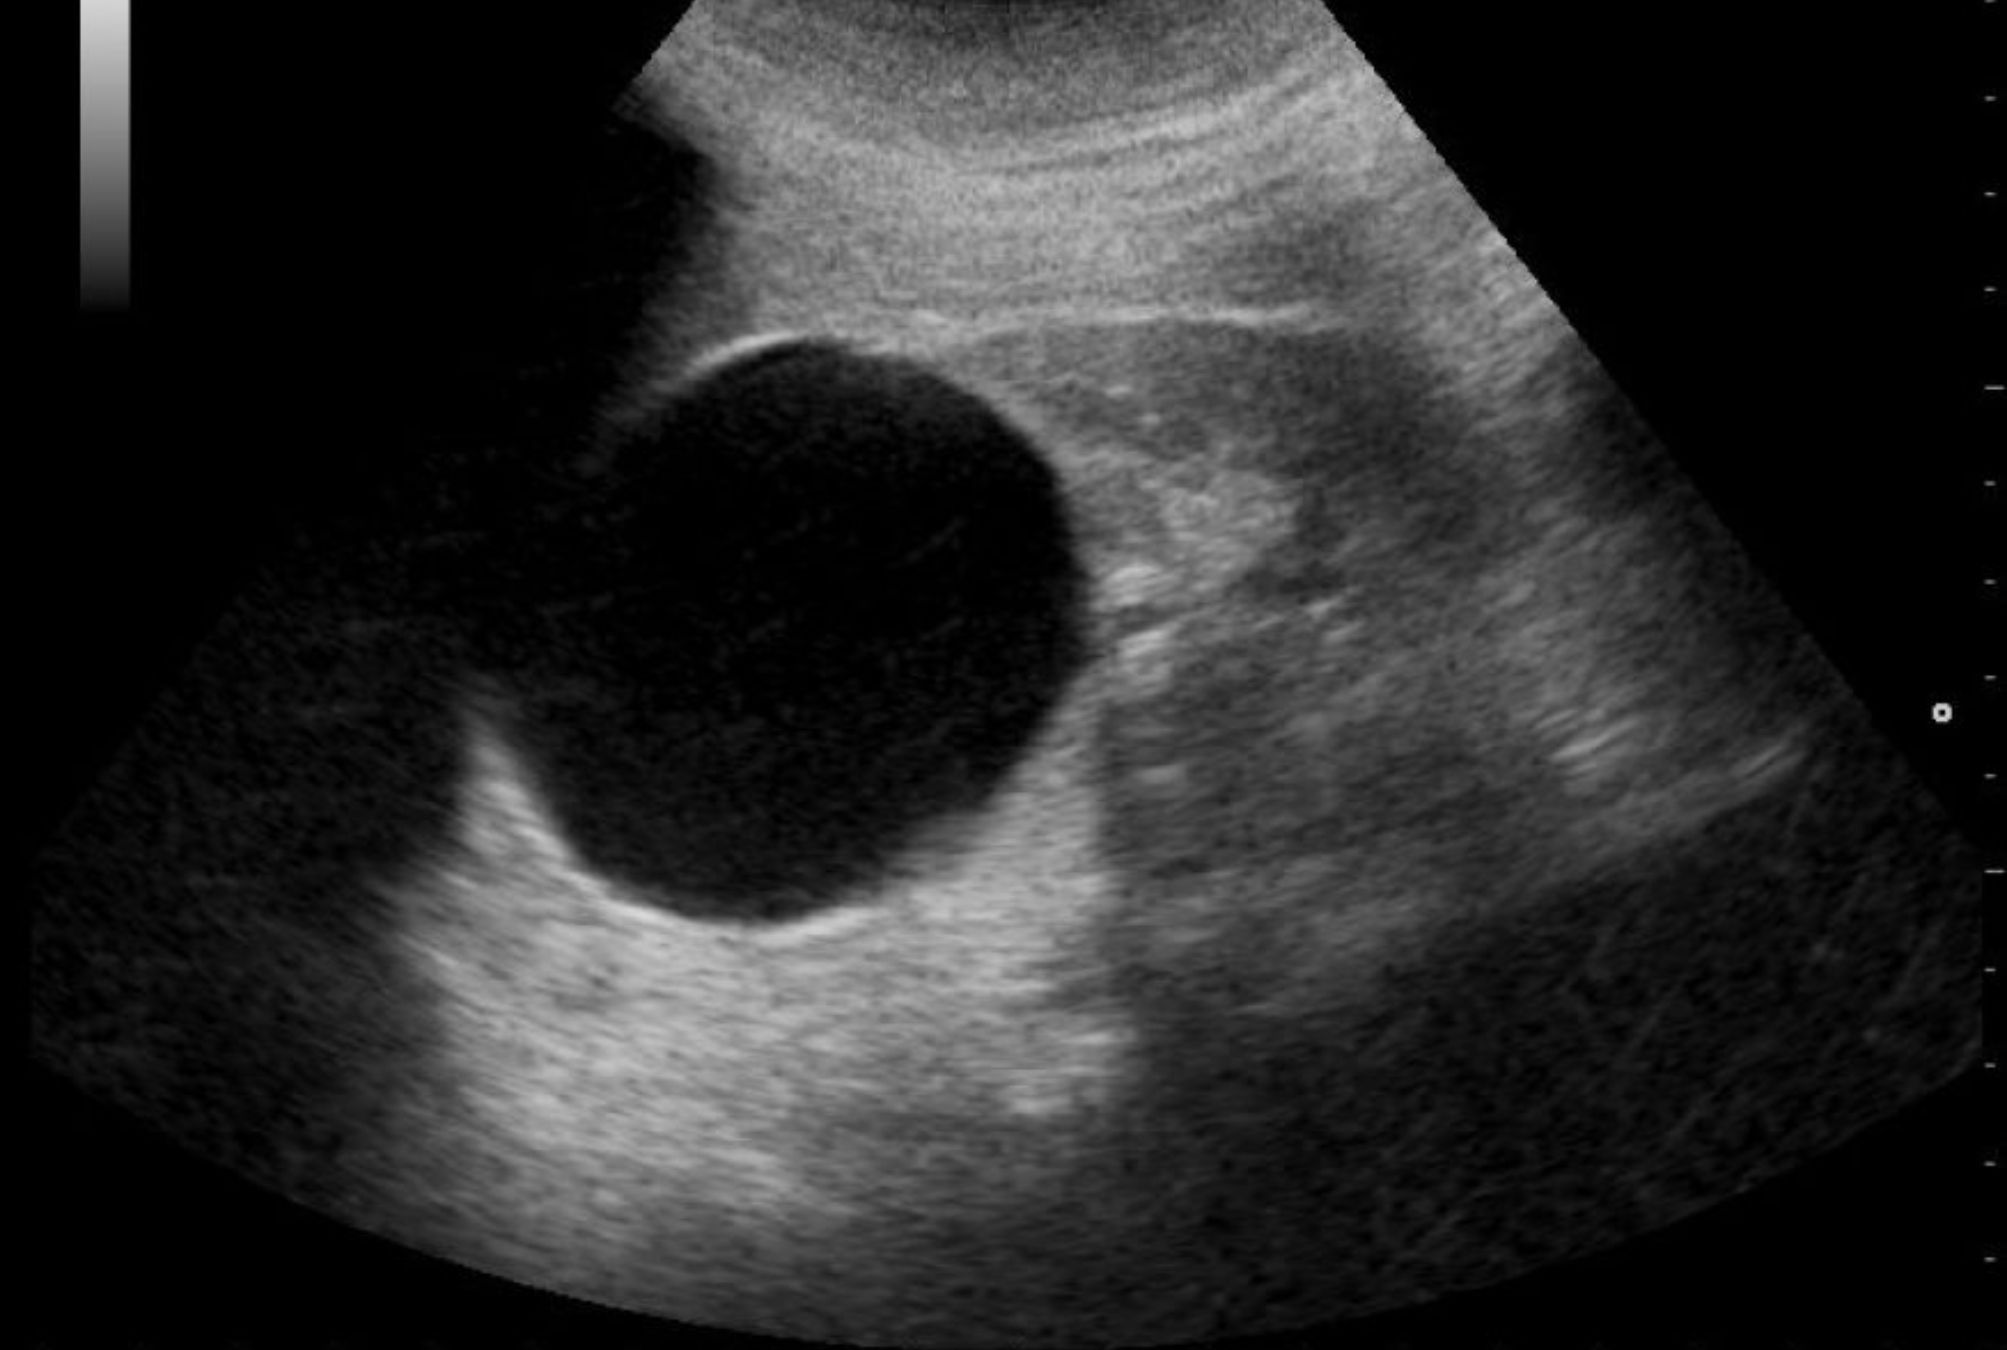

Η κύστη στο νεφρό είναι μια στρογγυλή θήκη με λείο ιστό και λεπτά τοιχώματα, η οποία συνήθως είναι γεμάτη με υγρό. Το υγρό που περιέχεται είναι διαυγές ή υποκίτρινο, εξηγεί ο Ανδρολόγος – Ουρολόγος Δρ. Α. Λέκας. Μπορεί να είναι μια ή περισσότερες και να εμφανιστούν στον ένα ή και στους 2 νεφρούς. Τις περισσότερες φορές είναι καλοήθης και η εμφάνισή της είναι αρκετά συχνή.

Πραγματοποιείται μια κλινική εξέταση ώστε να αξιολογηθούν τα συμπτώματα, αφού πρωτίστως ληφθεί το ιστορικό του ασθενούς. Επιπλέον, εάν κρίνει απαραίτητο ο ιατρός, θα διενεργηθούν απεικονιστικές εξετάσεις, όπως το υπερηχογράφημα, η μαγνητική τομογραφία (MRI) και η αξονική τομογραφία (CT). Αιματολογικός έλεγχος μπορεί να πραγματοποιηθεί επίσης, ώστε να εξακριβωθεί πόσο καλά λειτουργούν οι νεφροί.

Για την απλή κύστη στο νεφρό δεν χρειάζεται κάποια θεραπεία. Αρκεί η παρακολούθηση ανα περιόδους με υπερήχους. Στην περίπτωση που η κύστη είναι πολύ μεγάλη και δημιουργεί προβλήματα στον ασθενή, κρίνεται απαραίτητη η παρέμβαση. Προτιμάται η σκληροθεραπεία. Ο ιατρός τρυπά την κύστη με μια μακριά βελόνα που εισάγεται μέσω του δέρματος, χρησιμοποιώντας υπερήχους για καθοδήγηση.